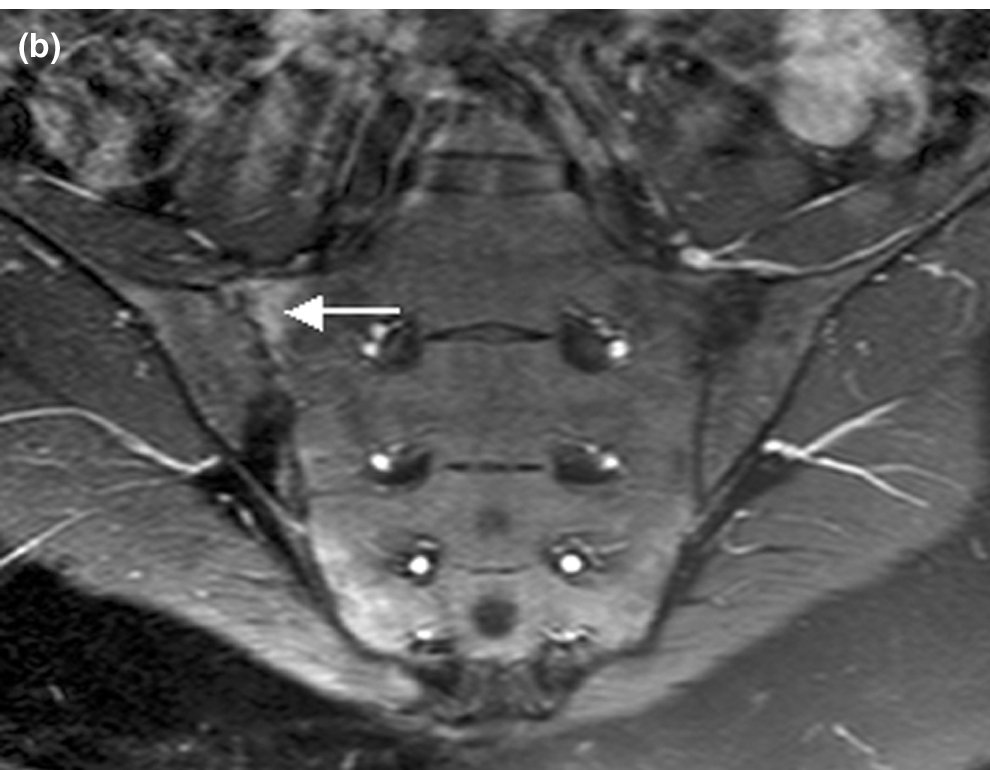

The sacroiliac joints can be imaged using MRI, mainly to exclude unusual pathologies (Infection, Stress Fracture).